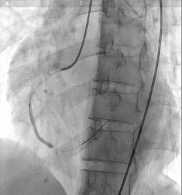

Left main artery is a 3.0 mm vessel without disease. Left anterior descending artery is a 2.5 mm vessel with tightest lesion of 70-80% tubular stenosis at the mid segment and left circumflex artery is a 2.5 mm vessel with a 80-90% tubular stenosis at the midsegment. Right coronary artery is a is a 2.5 mm diffusely diseased vessel with tightest lesion of 80-90% at the proximal. The AV continuation is a 2.0 mm vessel with luminal irregularities.

Percutaneous coronary intervention was initiated. A Xience Alpine 3.0 x 38mm drug-eluting stent (DES) was positioned at the mid to distal RCA and deployed at 16 atm and post-dilated using the same stent balloon inflated at 18 atm. Another Evermine 3.5 x 48mm drug-eluting stent (DES) was positioned at the proximal RCA and deployed at 18 atm and post-dilated using the same stent balloon inflated at 18 atm. Further dilation of the distal RCA was done using a Mini Trek 2.0 x 15mm balloon and inflated at 12 atm. However, j ust a few minutes after placing the stent. There was noted recurrence of the ST elevation on the cardiac monitor. A second look angiogram was immediately performed to check the patency of the stents. Immediately, manual distal displacement using the same stent balloon was done to displace the thrombus. Repeat angiogram showed TIMI II flow on the right coronary artery and resolution of the ST segment elevation.